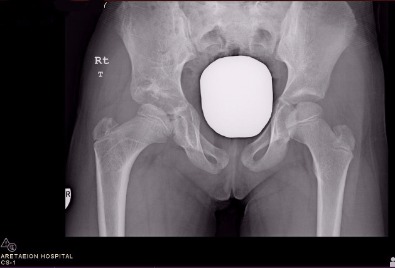

Congenital Hip Dislocation

Pre-operative x-rays of a three and a half year old in Cyprus who presented with a limp because of congenital dislocation of the right hip

Latest post-op xrays after open reduction pelvic and femoral osteotomies four years down the line - The patient has a normal gait